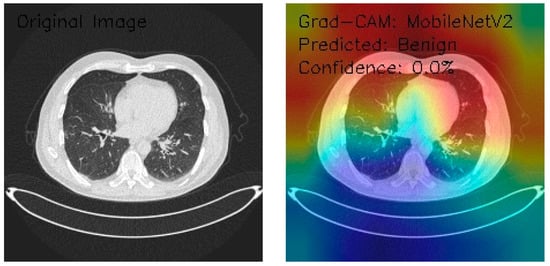

Analysis of MobileNetV2 Performance on Lung CT Images with Grad-CAM Visualization

This analysis focuses on three axial chest CT images evaluated using MobileNetV2 architecture, a deep learning model known for its efficient performance in image classification and feature extraction tasks. Grad-CAM was employed to understand the model’s decision-making process better. Grad-CAM is a visualization technique that highlights the regions of the input image the model considers most relevant for making predictions. This study assesses the model’s classification performance by integrating these advanced methodologies. It provides visual insights into the areas of the CT images that influenced its decisions, offering valuable interpretability to the outcomes.

Figure 13 shows the CT image exhibiting interstitial markings, potentially indicative of underlying pathology. Grad-CAM visualization displays a diffuse activation pattern, predominantly focusing on the central and right lung fields, with distinct color gradations suggesting varying feature importance. The model classifies the image as Benign with a confidence score of 0.0%, reflecting uncertainty in its decision-making process. While the activation patterns highlight relevant anatomical regions, the low confidence score points to the need for recalibration of the model’s classification layers and confidence metrics to improve reliability and clinical applicability.

Figure 13.

This analysis evaluates three axial chest CT images processed by the MobileNetV2 architecture, leveraging Grad-CAM visualizations to assess model attention and classification. Image 1 highlights scattered nodular densities with bilateral peripheral and mediastinal activation, classified as Malignant with 0.0% confidence. Image 2, demonstrating interstitial markings, shows diffuse central and right lung activation, classified as Benign with 0.0% confidence. Image 3, featuring clear lung parenchyma, exhibits asymmetric activation in the right upper lung, classified as Malignant with a slightly higher confidence (0.1%). The model’s confidence levels remain critically low despite consistent feature detection and focused attention patterns, indicating calibration and classification inefficiencies.

Key findings reveal MobileNetV2’s sensitivity to anatomical variations and clear feature recognition but with limited reliability for clinical applications. Recommendations include the recalibration of confidence metrics, architecture-specific optimizations, and validation through ensemble methods and expert radiological input. These refinements address classification uncertainty and enhance the model’s applicability to lung CT image analysis.